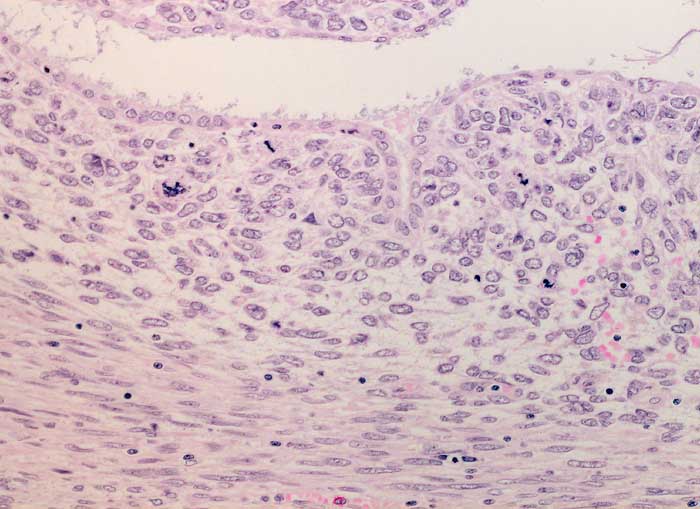

PathoPic – image database / PathoPic ID 6288 - Adenosarkom

Adenosarkom

maligner Tumor

Uterus

In diesem Bildausschnitt ist eine von gutartigem Epithel ausgekleidete Zyste erkennbar. Das angrenzende Stroma ist verdichtet (Kambiumschicht), weist ausgeprägte Atypien und mehrere, teils atypische Mitosen auf.

Postmenopausale Blutungsstörung, sonographisch suspekter Endometriumbefund, klinisch V.a. Endometriumkarzinom.

Histologie

200